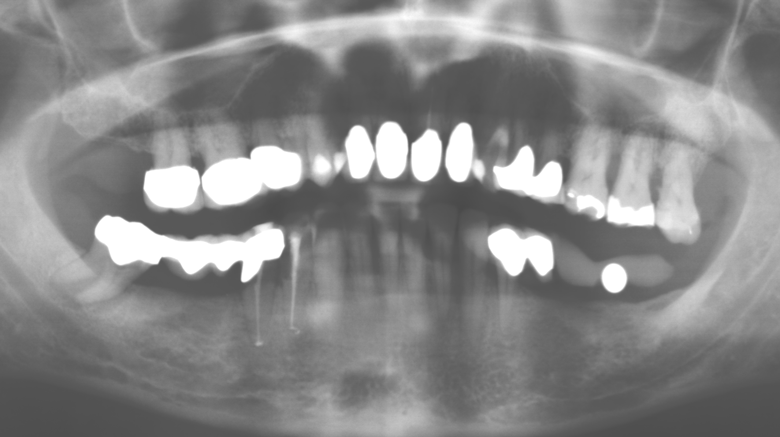

Fig. 1: Panoramic radiograph of initial situation in 2004.

Description of patient case

A 52-year-old patient presented in our clinic for the first time in 2004 following tooth loss in the third quadrant, expressing a desire for a new prosthetic restoration. Periodontal and radiological diagnostics revealed the need for extensive periodontological treatment. In addition, teeth 48, 28 and 27 were attributed a very poor prognosis and were subsequently extracted (Fig. 1). Following the successfully completed, systematic periodontological treatment, a fixed dental implant was inserted with the introduction of five implants in tooth regions 35, 36, 37, 46 and 47. Prosthetic treatment of the natural teeth was effected with veneered zirconium dioxide ceramic crowns; the implants were composed of two-piece, individual zirconium dioxide abutments and similarly veneered crowns made of a zirconium dioxide ceramic (Cercon base colored, Dentsply Sirona Lab). Definitive insertion of the prosthetic restoration occurred in 2005.

The ten-year check-up revealed no indications of advancing clinical attachment loss or peri-implant bone substance loss (Fig. 3).

Fig. 3: Panoramic radiograph after ten years with implants.